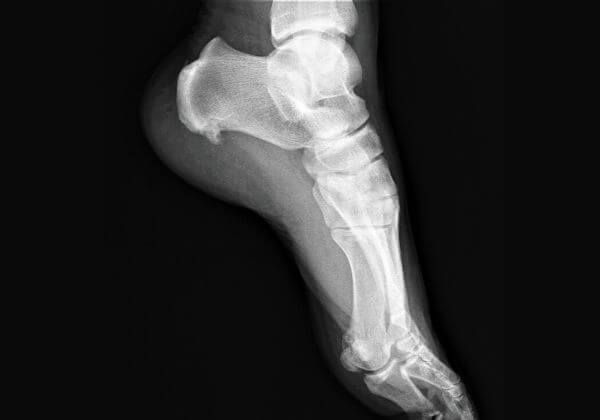

Our bones support us and allow us to move. They cushion our brain, heart, stomach, and other vital organs from injury. Our bones act as storage for vital minerals which is why it's critical to keep them healthy as you age.